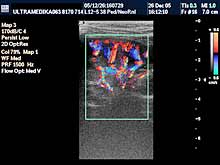

Pregled dece zahteva posebno setovanje aparata tj. primenu gotovih

automatskih programa za posebne preglede kao što su mozak, organi

stomaka i male karlice, srca i mekih tkiva. Ne mogu se adekvatno

pregledati deca sa aparatima koji poseduju programe samo za odrasle

pacijente. U proseku oko 15 ultrazvučnih programa postoji za kompletan

ultrazvučni pregled dece. Njihovo nepostojanje je obično jedan od

razloga za netačne dijagnoze u dece.

Šesti princip:

Ultrazvučni pregled kod dece zahteva ultrazvučne sonde određene

rezolucije kao obavezni preduslov pouzdanog i tačnog pregleda. Sonde

od 5-12 MHz su neophodne u pregledu dece do 10 godine života. Za

preglede mekih tkiva (limfnih žlezda , pljuvačnih žlezda, štitne

žlezde, kože i potkožnog tkiva) , krvnih sudova, mišićno-zglobnog

sistema ova sonda je neophodna bez obzira na uzrast pacijenata.

Sedmi princip:

I kod UZ pregleda u dece važe iste karakteristike savremene

dijagnostike koja je zasnovana na primeni Broad band tehnike, HDI

tehnike, Sono CT (kompjuterizovane ultrazvučne tomografije), Xres,

Broad band kolor doplera (CD), kolor power angio moda i dopplera CPA i

CPD, 3D Sono CT, Panorama moda, Harmonik moda. |